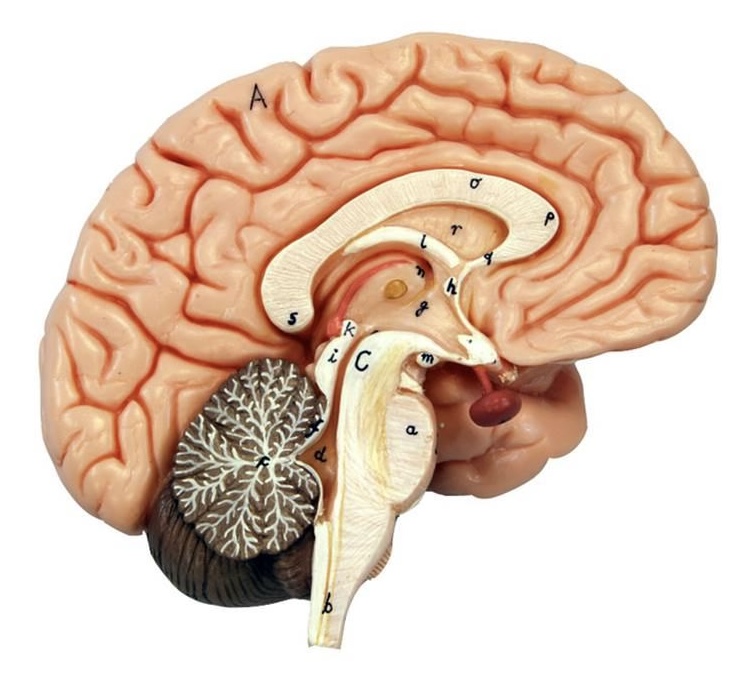

What is C?

3rd ventricle

What is B?

cerebral aqueduct

What is A?

4th ventricle

What is below A at the very end?

central canal (spinal cord)

What is C?

midbrain

tectum (corpora quadrigemina): superior colliculus

tectum (corpora quadrigemina): inferior colliculus

What is a?

pons

medulla oblongata

intermediate mass of thalamus

hypothalamus

What is the pink bulb?

pineal gland

corpus callosum

fornix

What is A?

cerebral cortex

cerebral tracts

cerebral hemispheres

longitudinal fissure

What are these ridges?

gyri

What are these shallow grooves?

sulci

Divides parietal from frontal lobe

central sulcus

precentral gyrus

postcentral gyrus